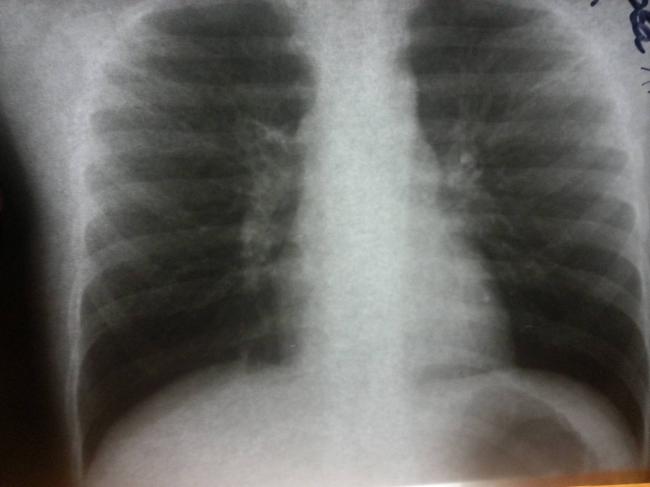

Основным методом диагностики прикорневой пневмонии являются рентгенологические методы исследования. На рентгенограммах врач может увидеть локализацию воспаления, дифференцировать прикорневое воспаление лёгких от других заболеваний дыхательных путей. Но при прикорневой пневмонии интерпретация рентгенографического исследования может быть затруднительной. Затемнение от воспалённого очага часто наслаивается на корень лёгкого. В результате легочный корень на рентгеновском снимке «расширяется», что может указывать на новообразование или туберкулёз.

Рентгенологическое исследование: имеет типичный образ неоднородной инфильтрации, состоящей из множественных конфлюэнтных, не резко разграниченных локализаций.